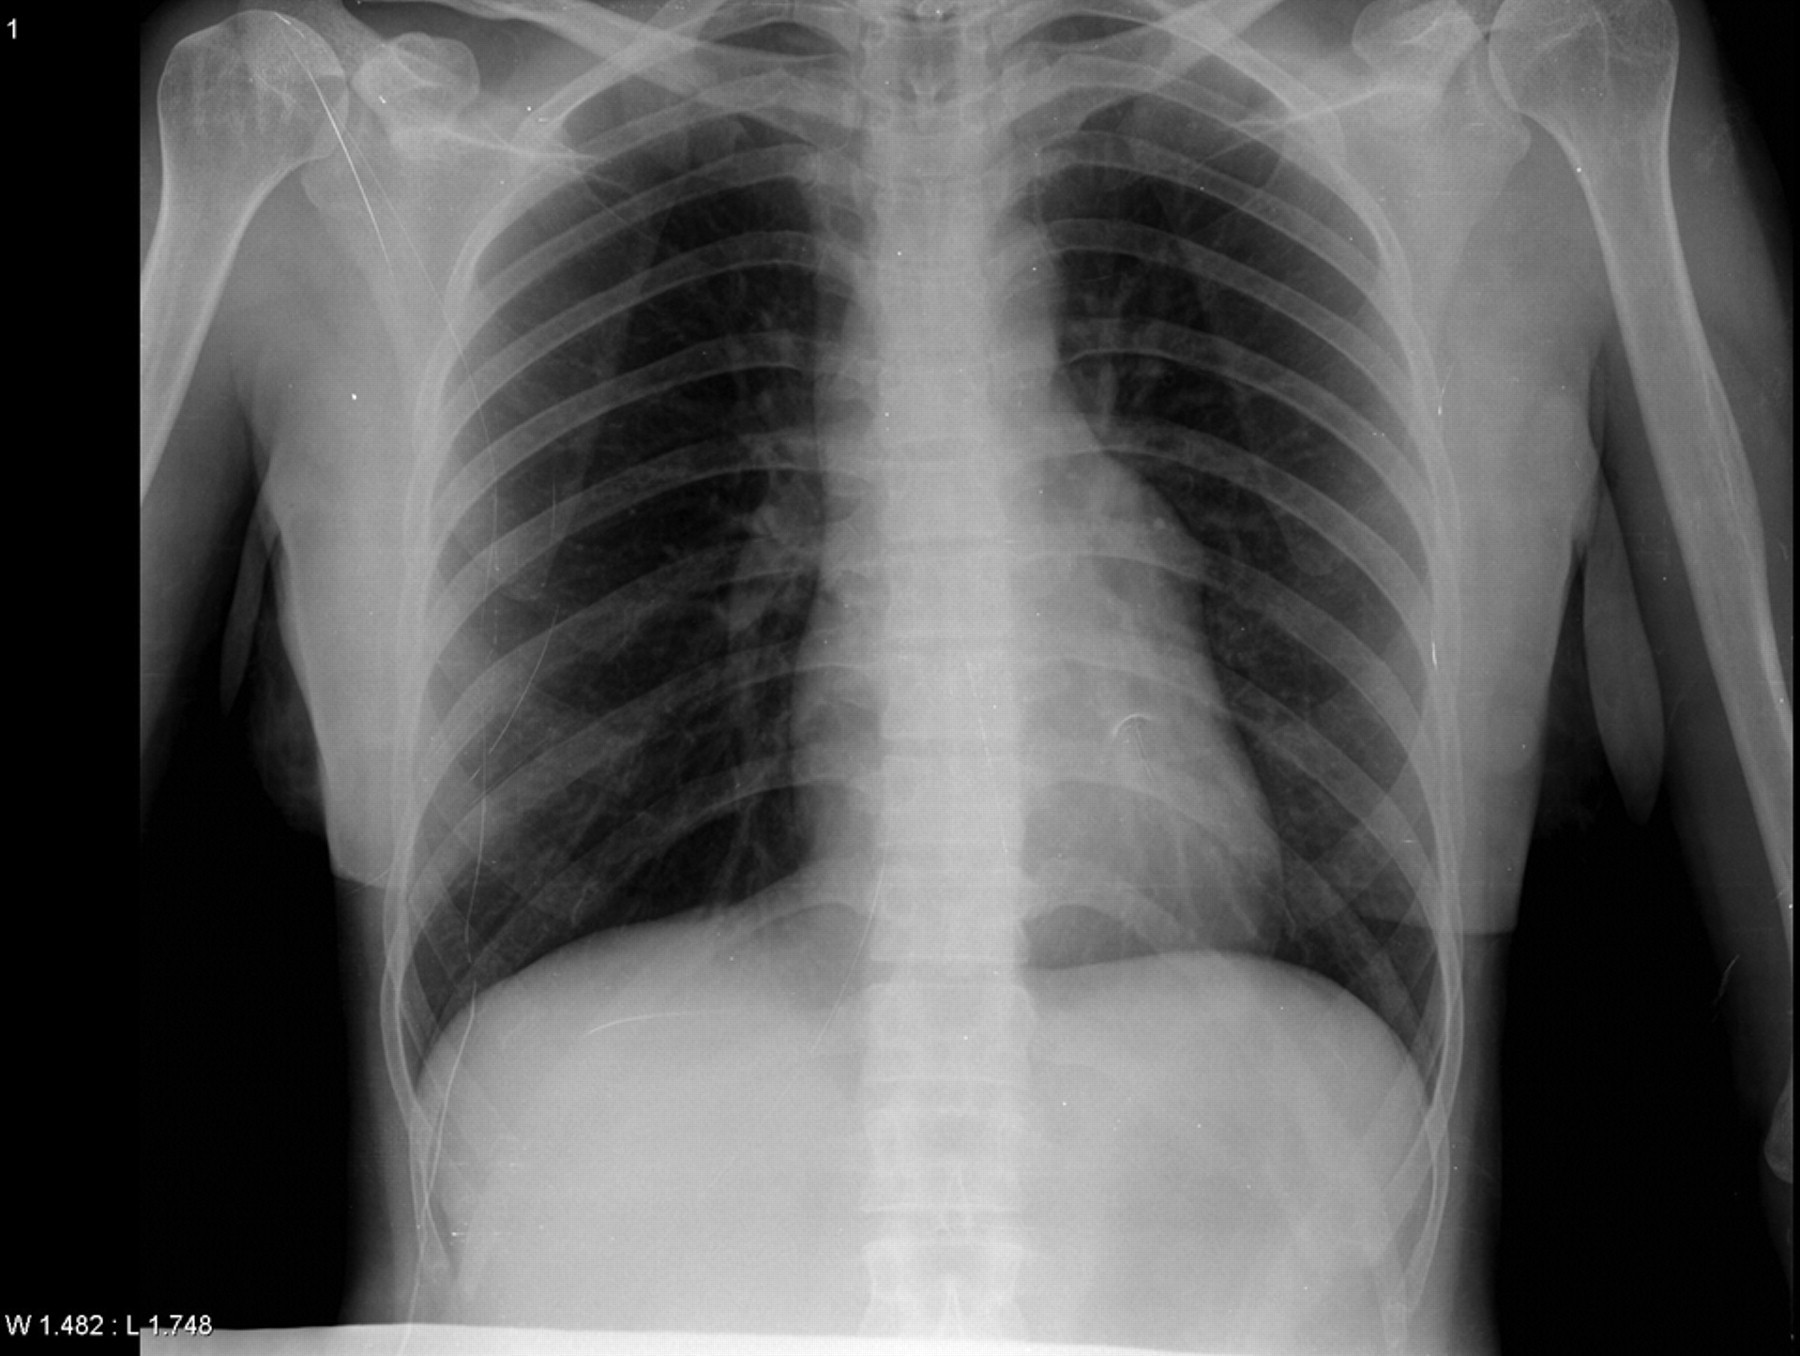

İlk önce koronavirüsten şüphelenilerek hastaneye yatırılan akduman'a yapılan koronavirüs testinin sonucu negatif çıktı. kendi isteği üzerine hastaneden taburcu edilen akduman, özel bir hastanede bronkoskopi yaptırdı.

Ciğerlerimde buzlanma olduğunu söyleyip, koronavirüs testine gönderdiler. yatışımı yaptılar. testimin negatif çıktığını ama birkaç gün hastanede kalmam gerektiğini söylediler. daha sonra özel bir hastaneye gittim. orada ciğerlerimde ceviz olduğu tespit edildi. ceviz çıkarıldıktan sonra normale döndüm. şu anda sağlık durumum iyi’ dedi.

Göğüs hastalıkları uzmanı arzu ertem cengiz de hasta nefes darlığı şikayetiyle başvurduğunu belirterek, şu ifadeleri kullandı: ‘koronavirüs açısından değerlendirmelerimizi yaptık ama herhangi bir bulguya rastlayamadık. hastanın hikayesini derinleştirince, suyun içine koyduğu cevizin akciğere kaçabileceğini düşündük ve bronkoskopi işlemi yaptık. sol akciğeri tıkayan cevizi gördük. uygun ekipmanlarla cevizi çıkararak hastayı rahatlattık. sonrasında hasta iki gün kadar antibiyotik tedavisi aldı. belirgin olarak rahatladı. hasta iyi bir şekilde taburcu edilerek evine gönderildi.’